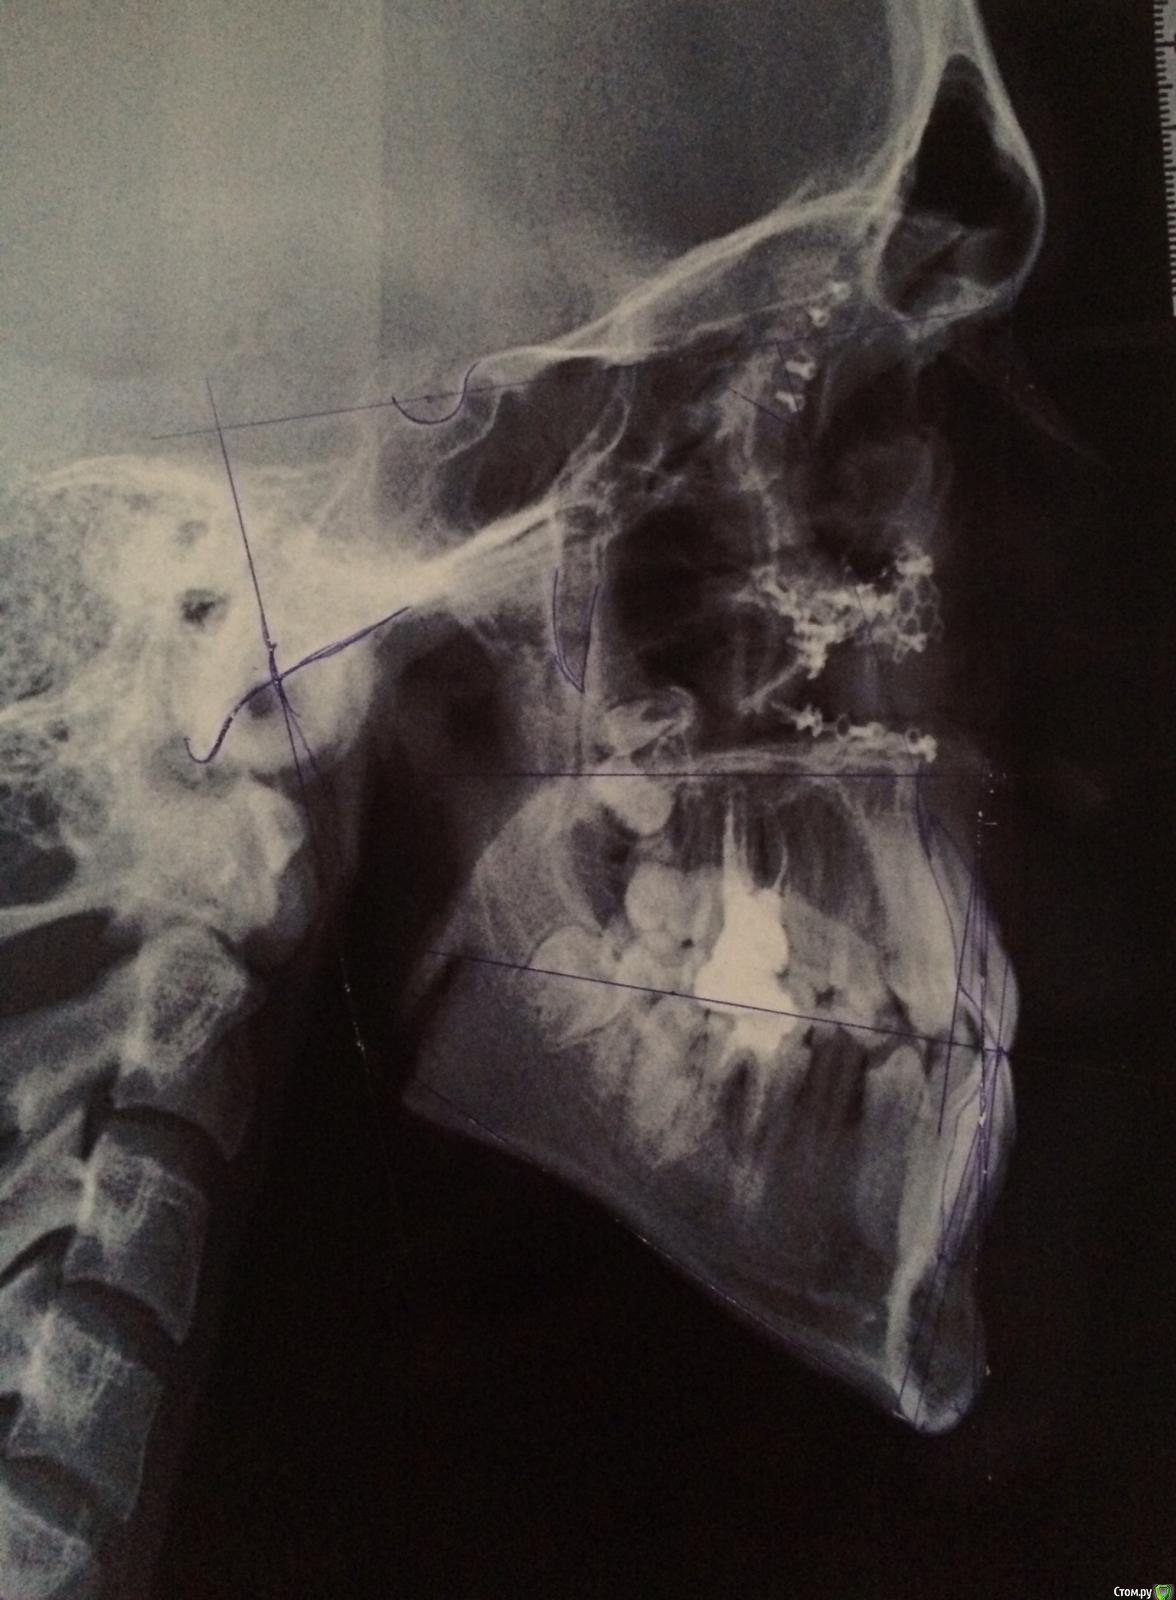

Maverick Опубликовано 29 августа, 2015 Поделиться Опубликовано 29 августа, 2015 (изменено) Доброго времени суток. В клинику обратился пациент. В детстве была травма лицевого скелета в возрасте 13 лет. Упали футбольные ворота. Было проведено хирургическое вмешательство по ре позиционировнию костных отломков скуловых, орбитальных костей. Были даны рекомендации вернуться через год на повторный осмотр, но так получилось, что этого сделано не было. Что имеем по факту. При осмотре лица заметно девиация нижней челюсти в левую сторону, не критичную,обычный человек не обратит внимание, но бросающуюся в глаза если смотреть в кресле. Из данных трг анализа , скелетный 3 класс, wits -6(не очень критично ), увеличенный размер нижней челюсти по сравнению с нормой, ANB -1,5 , ретроположение всего лицевого скелета. Строго вертикальный тип роста, долихофациальный. Sn-mp 41. В полости рта все куда хуже, суженная верхняя челюсть, нехватка ширины порядка 7 мм в области премоляров и 5 мм в области моляров, благодаря чему мы получаем перекретный прикус, первый класс по молярам и клыкам слева и третий справа, вторичная адентия на нижней челюсти 46. Смещение центральной линии влево на целый резец. И еще приятный бонус это кант окклюзионной плоскости, во втором квадранте вверх в первом вниз. Интересно мнение коллег. Изменено 29 августа, 2015 пользователем Maverick Ссылка на комментарий

Maverick Опубликовано 29 августа, 2015 Автор Поделиться Опубликовано 29 августа, 2015 Оптг у пациентов к сожалению.17 лет на данный момент. 45 зуб так интересно сместился что и меня ввел в небольшой ступор. 46 был удален давно. Фоток нет к сожалению пока нет, профиль прямой, в фас видно увеличение нижней трети лица. Разница в длине ветвей присутствует слева длиннее на 3 мм. Девяток нет ) это все качество снимков. Пациент впринципе не радикально хирургический. Можно провести достойную компенсацию. В мыслях была микроимплантация для ротации плоскости и конечно расширение верхнего зубного ряда что само собой разумеется., думаю тогда нижняя челюсть заняла бы оптимальную позицию, а не вынужденную ,как сейчас и смещение не было бы так выражено. Вся информация что имеется на данный момент представлена. Ссылка на комментарий